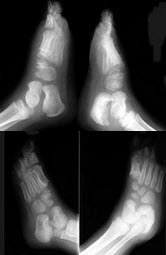

163、单项选择题

女,5岁,左踝疼痛,结合图像,最可能的诊断是()

A.创伤性关节炎

B.退行性骨关节病

C.神经性关节病

D.风湿性关节炎

E.痛风